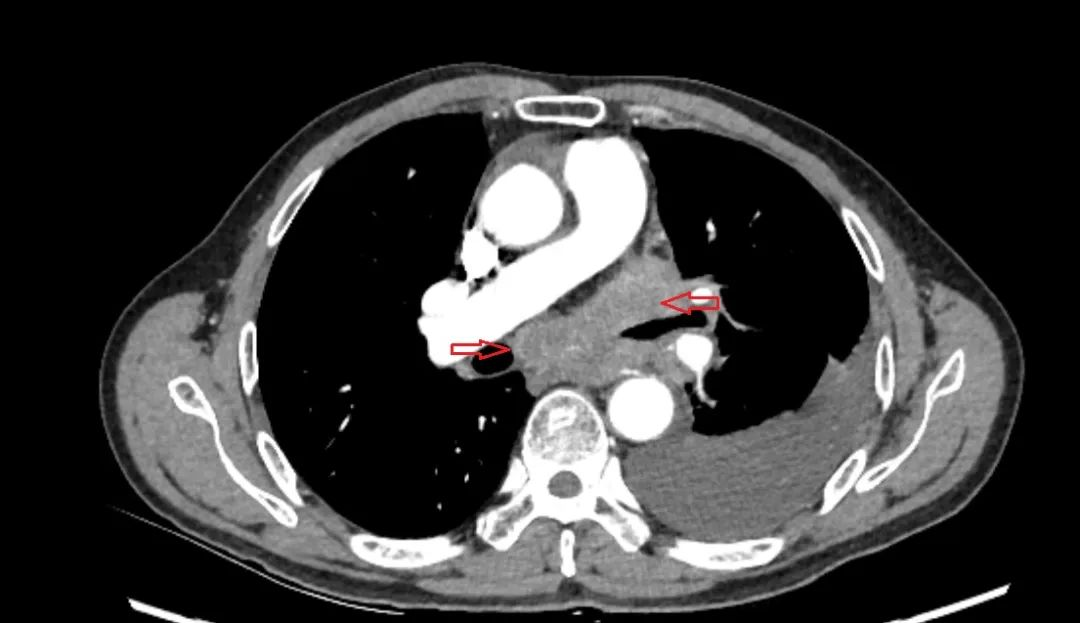

病例三

患者因发现右下肺占位入院,胸部增强CT提示右下肺肿物并纵隔淋巴结肿大,超声支气管镜下见11R淋巴结肿大,紧邻心脏,成功穿刺取得足够标本并确诊鳞癌,术中出血仅约1ml。

病例四

患者因咳嗽、气促入院,胸部增强CT见左下肺肿物并多发淋巴结肿大,支气管镜见粘膜浸润性改变为主,活检病理阴性,遂行超声支气管镜下7#+10L淋巴结穿刺活检,病理结果证实为鳞癌。